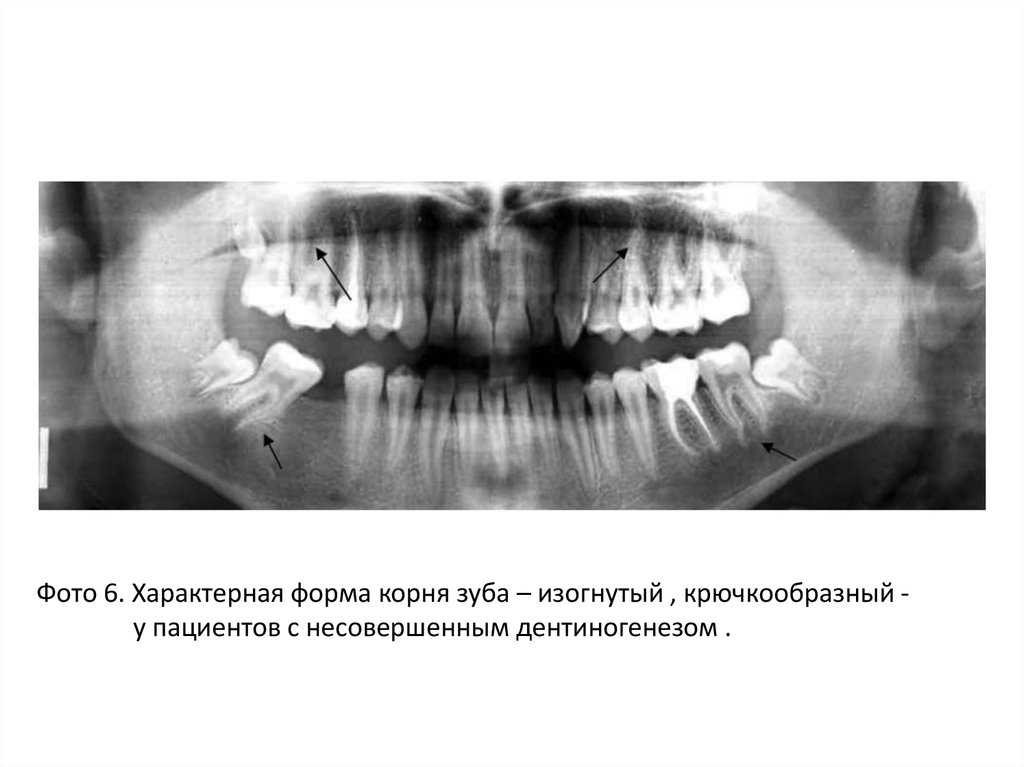

Фото 6. Характерная форма корня зуба – изогнутый , крючкообразный у пациентов с несовершенным дентиногенезом .